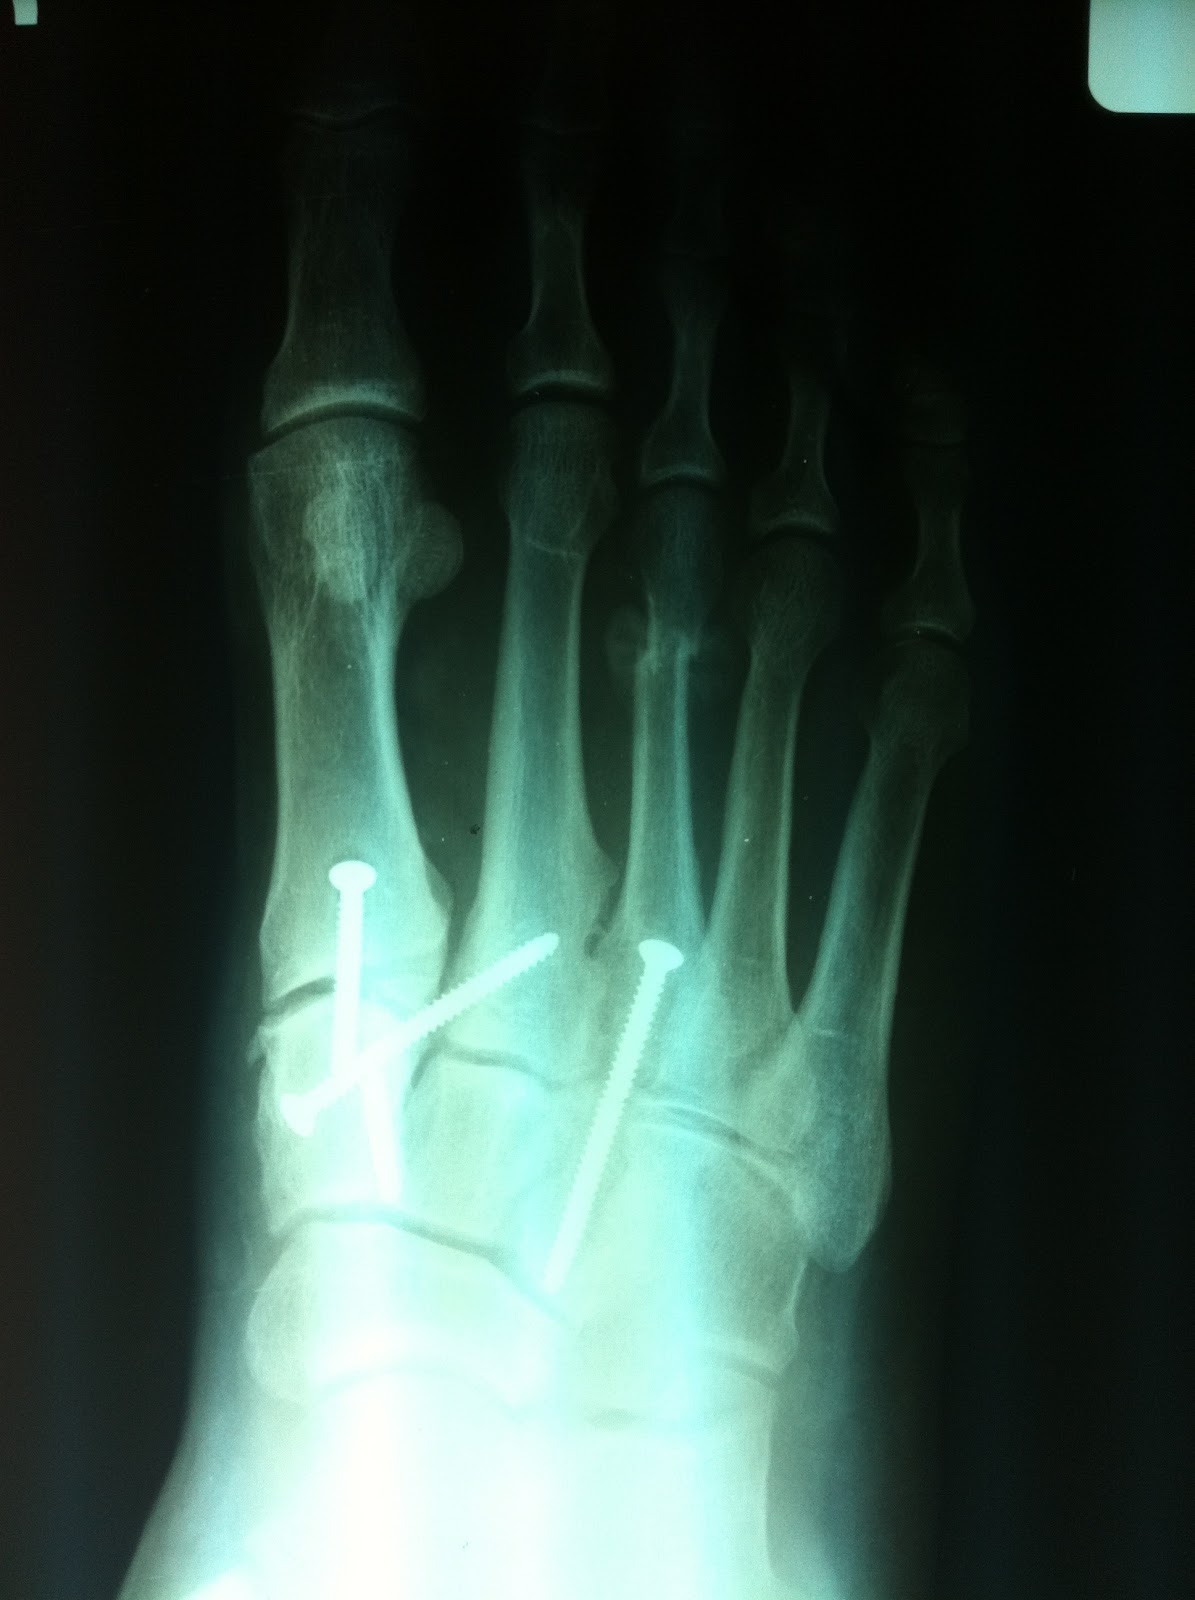

Jones Fracture S92.353A 825.25 | eORIF

Jones Fracture S92.353A 825.25 | eORIF from www.eorif.com